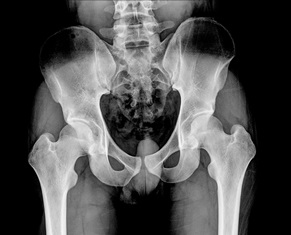

After an auto accident, a victim with a pelvic fracture will likely experience tenderness in the area and difficulty walking or moving the lower parts of the body. Abdominal pain, bleeding from the rectum or genital area, and difficulty urinating are also possibilities. The injury can be diagnosed with an X-ray and CT scan.

A broken pelvis is not synonymous with a broken hip, but someone with a broken pelvis may also have a hip fracture.